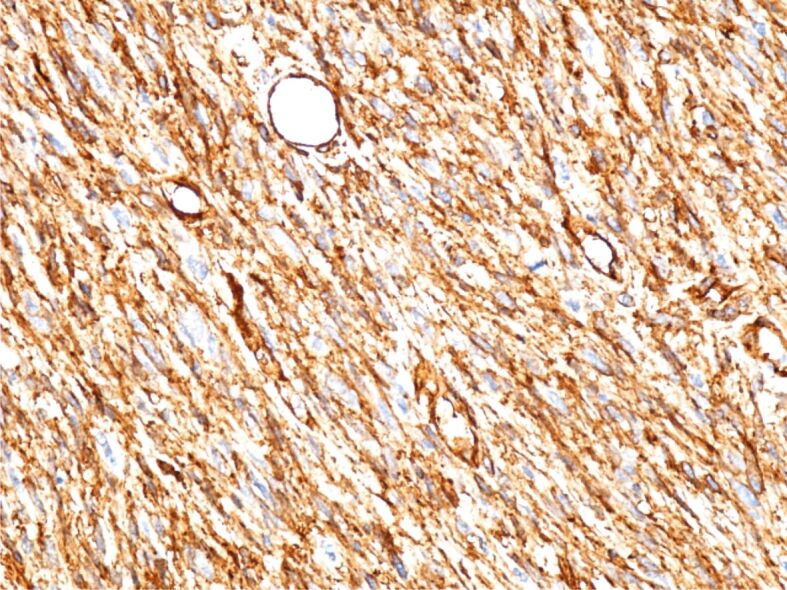

Solitary fibrous tumor (SFT) is a rare mesenchymal tumor that is quite aggressive and prone to recurrence and metastasis. Most SFTs are benign, but the identification of the histological features that define the dedifferentiation of SFTs can predict the aggressiveness of the tumor and the presence of a reserved prognosis. We present a rare case of conventional SFTs with features of malignancy and highlight the diagnostic and therapeutic difficulties related to this case. Computed tomography aspect suggested a possible gastrointestinal stromal tumor. Surgical intervention was performed through median laparotomy and a tumor of approximately 15∕12 cm was found, developed from the level of the right retroperitoneal space, and pushing anteriorly the ascending colon, cecum, and terminal ileum. The immunohistochemical aspect correlated with the histopathological one suggests a SFT most likely malignant. In conclusion, the early diagnosis of SFTs is essential in establishing an appropriate treatment. Immunohistochemistry is indispensable in establishing the diagnosis of SFTs.

Abstract Image